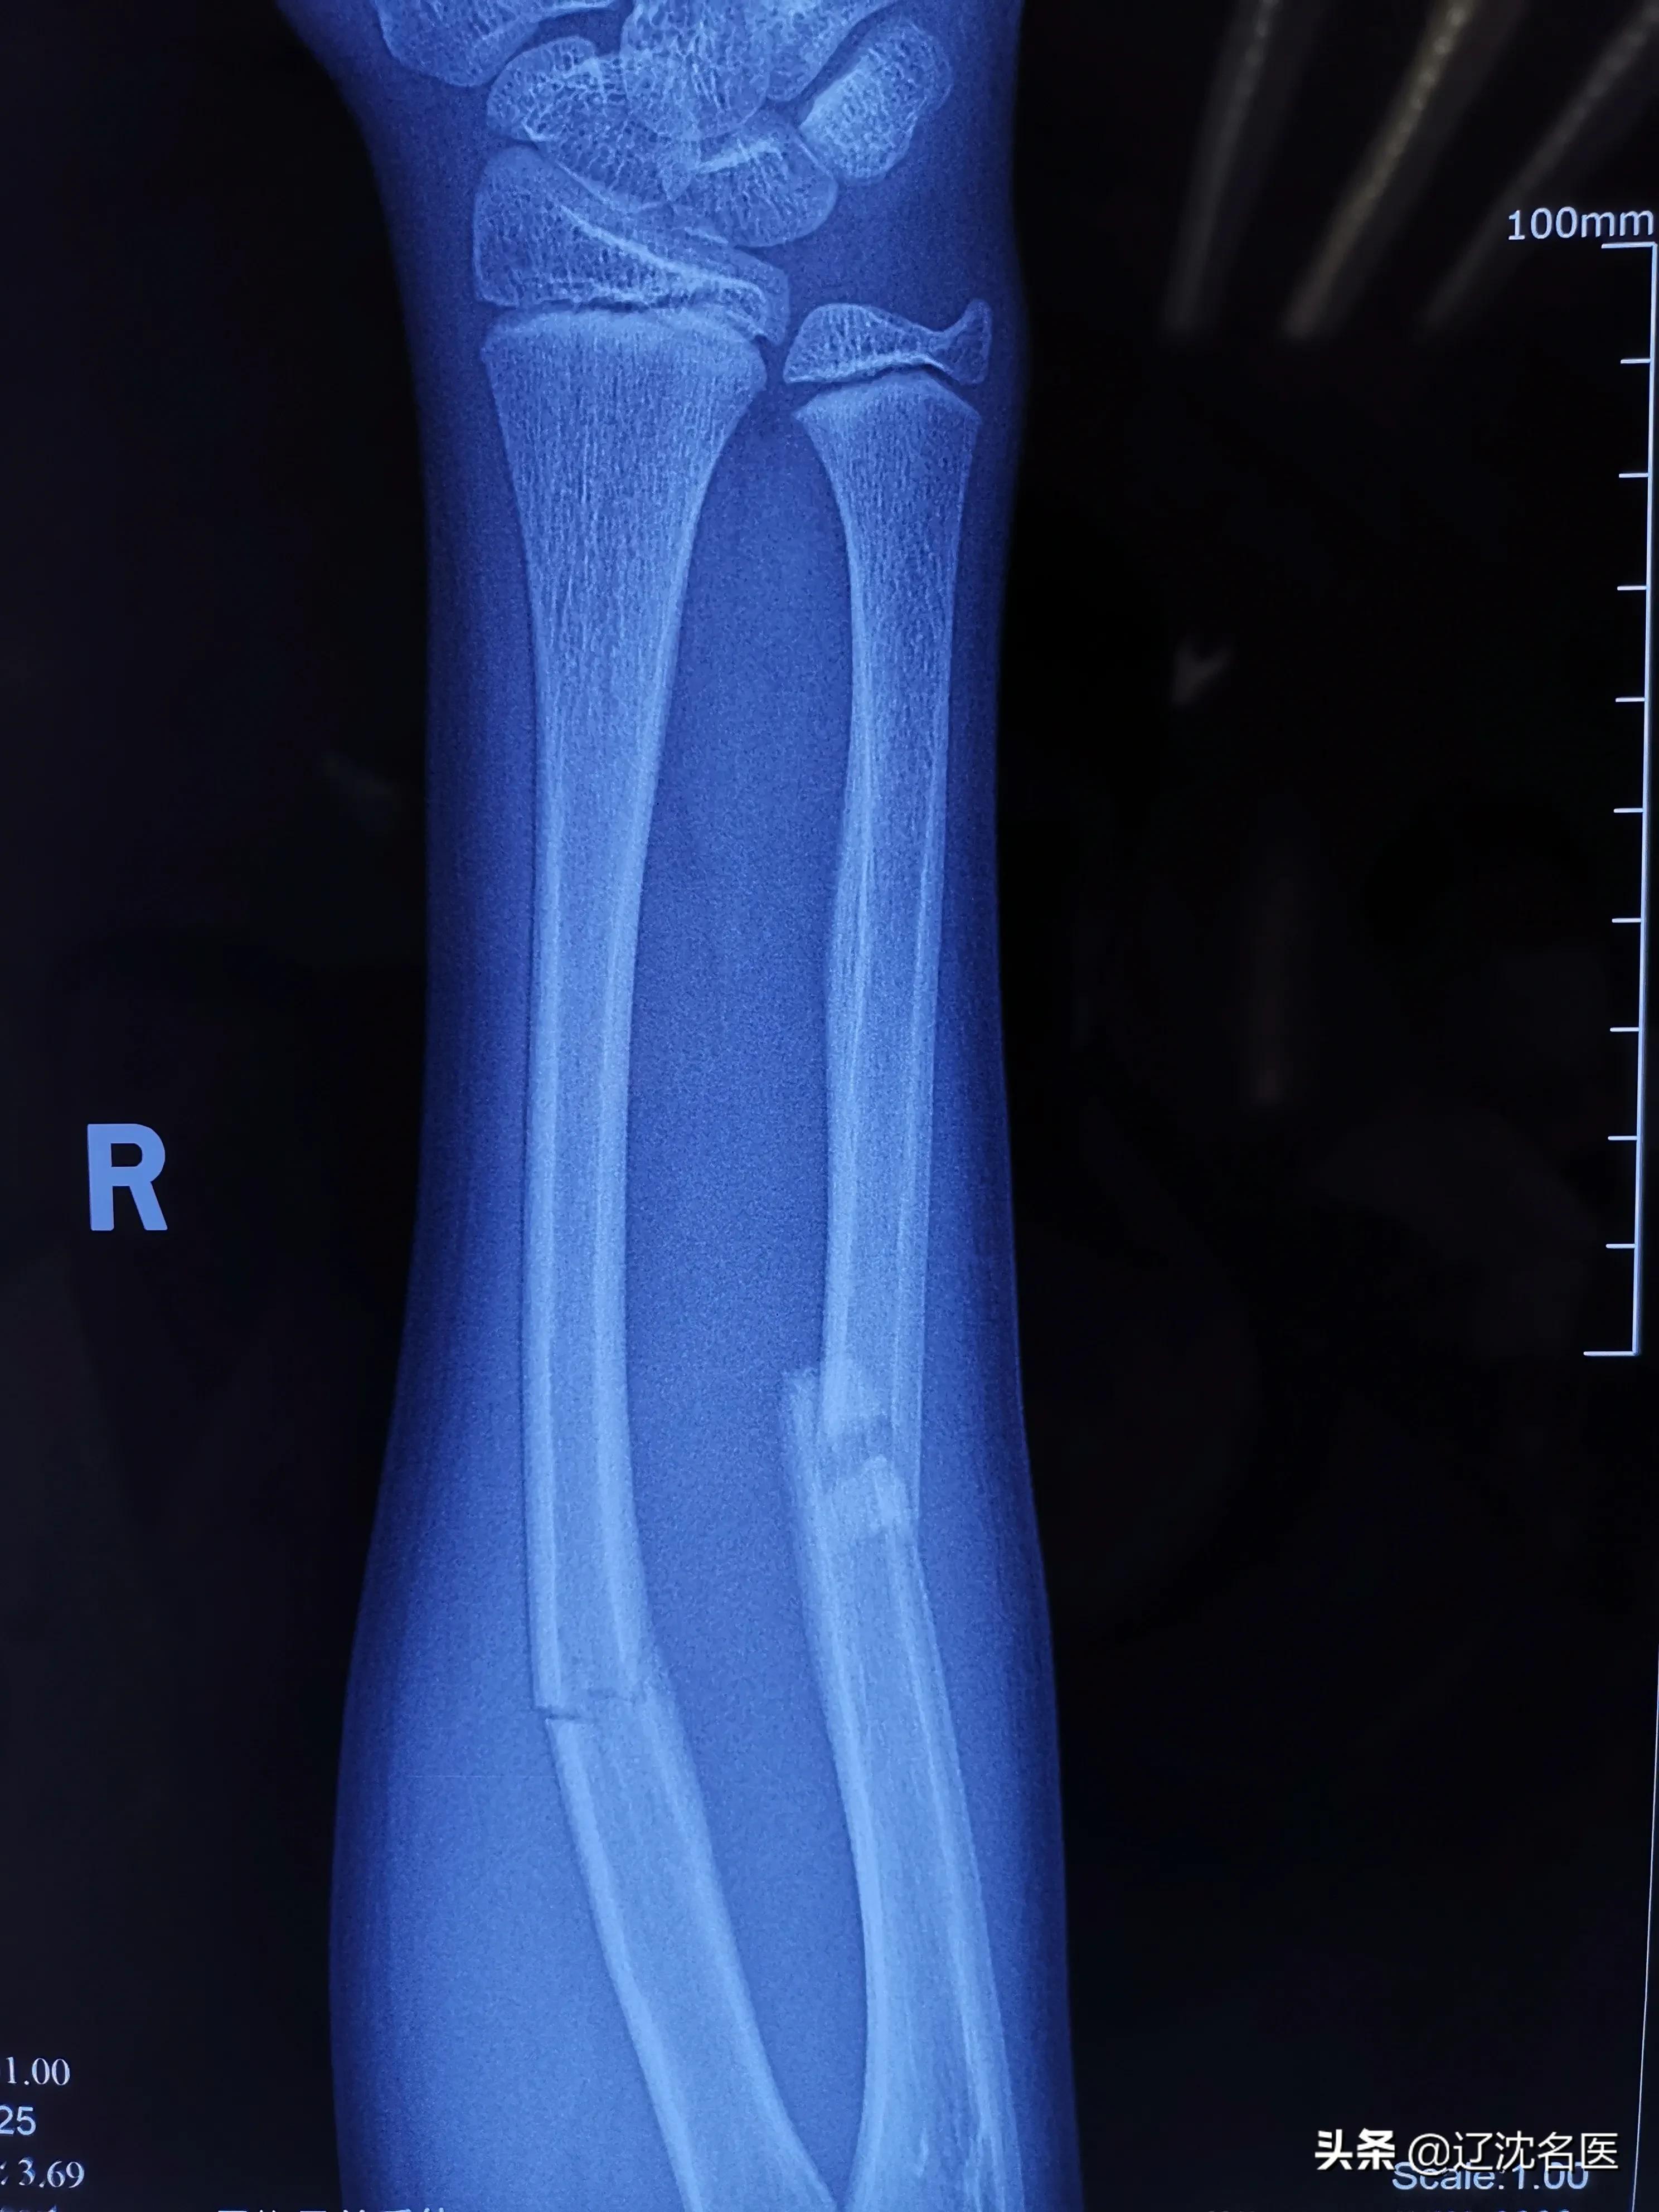

患者是一位12岁的小男孩,因骑自行车摔伤致右前臂肿胀、疼痛、活动受限,在父母焦急的陪伴下来到沈阳医学院附属中心医院急诊就诊,经X线检查诊断为“右尺、桡骨双骨折”。

骨折为不稳定骨折,移位明显,如果采用非手术治疗不能取得满意的复位效果,会影响患儿的上肢功能,必须进行手术治疗。

(术前X线:尺桡骨双骨折,短缩成角移位;腕部骨骺未闭合)